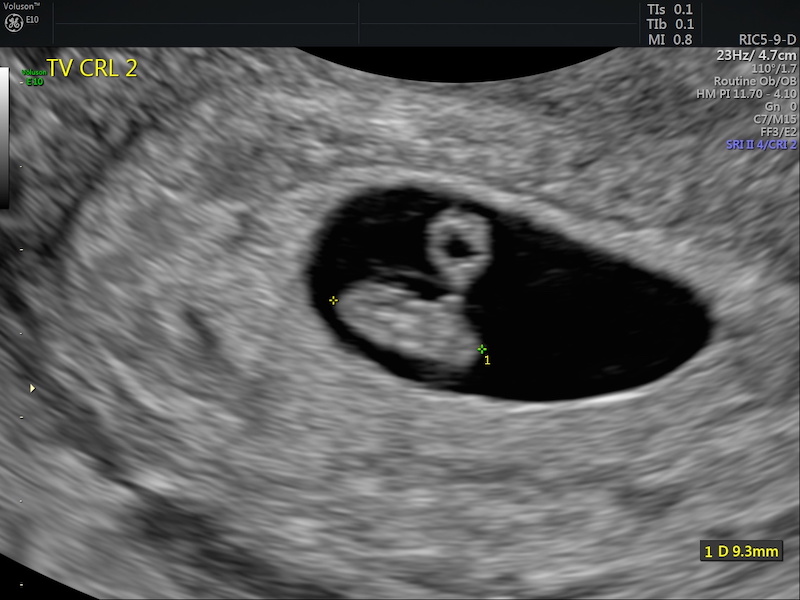

Hi! First of all, here’s a picture from the ultrasound I mentioned in my last pregnancy diary post! We were able to see the baby and his/her heartbeat 😍

Early pregnancy ultrasound

I had my first prenatal appointment yesterday! I was a little nervous beforehand because Niva had jumped on my stomach a few days prior and I was worried she could have hurt the baby. Hearing baby’s heartbeat during the appointment was extra sweet!